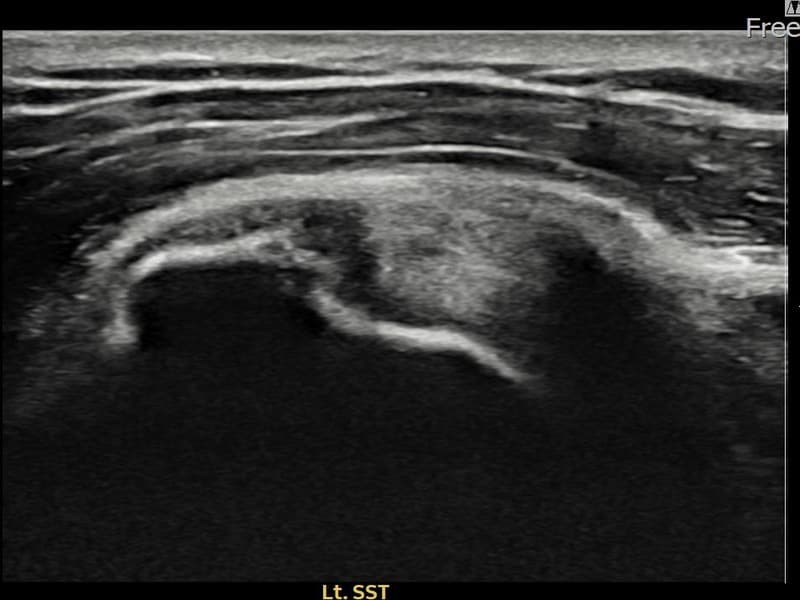

超音波検査にて左 棘上筋腱 部分断裂(7mm × 3mm (腱厚の約30%欠損))を確認。縫縮術施行後、腱の連続性が回復し、日常生活に復帰されました。

施術前

術前超音波にて左 棘上筋腱 部分断裂・左肩棘上筋腱のエコー不連続と腱欠損(7mm × 3mm (腱厚の約30%欠損))を確認。術後超音波では断裂部位が再生組織で充填され、腱の連続性回復とエコーパターンの正常化が確認されました。

持続する左肩痛で来院された患者様です。超音波検査にて左 棘上筋腱 部分断裂(欠損:7mm × 3mm (腱厚の約30%欠損))を確認し、超音波ガイド下で非手術的縫縮術を施行しました。術後は約4〜6週間のブレース装着の後、段階的なリハビリプログラムを実施。経過超音波で腱の連続性回復を確認し、患者様は無事に日常生活へ復帰されました。